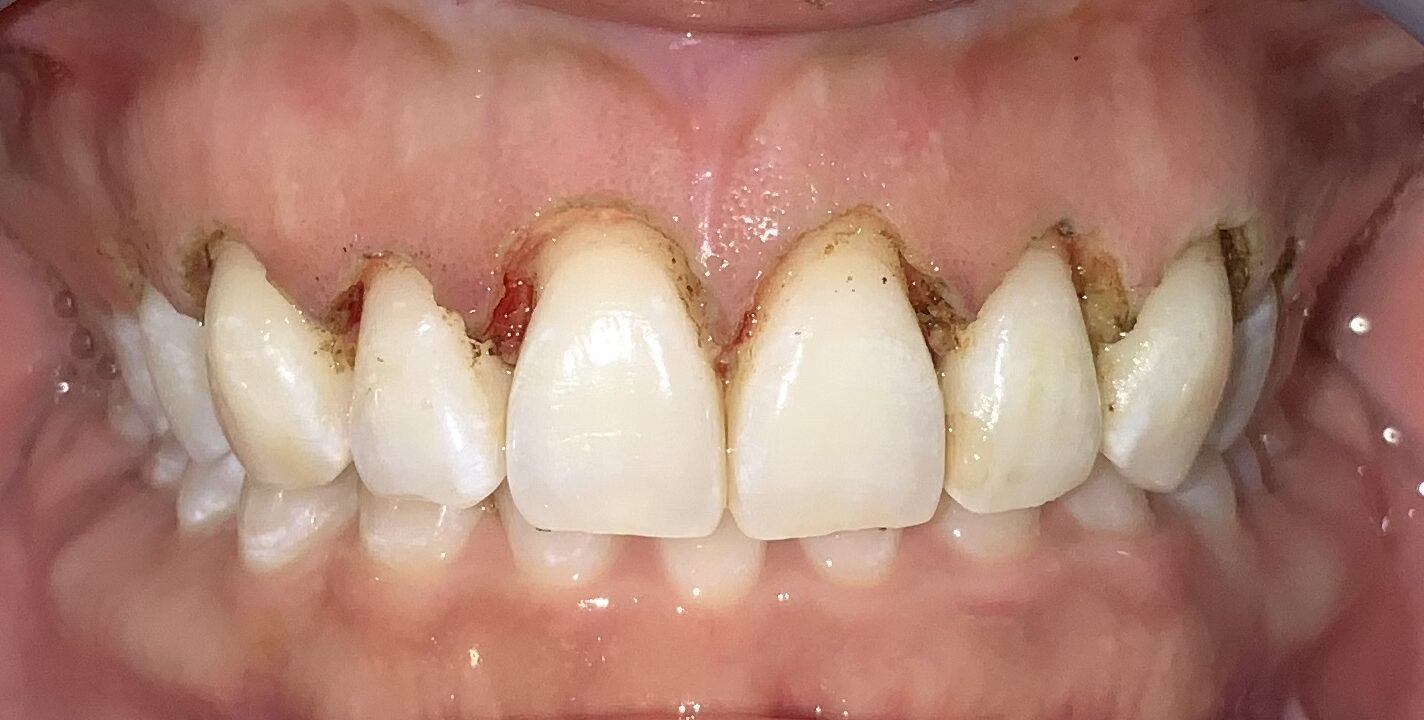

患者様のOKが出たので、すべての歯の治療を行いました。

歯ぐきの面積が少なくなって、笑った時の歯ぐきが見えなくなり、歯の形も、歯ぐきの形も綺麗に改善しました。

歯ぐきが一部黒ずんでいる部分は、数日で改善するのでご安心ください。